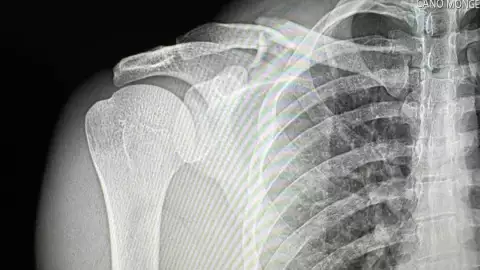

El reconocido exponente de los corridos tumbados, Natanael Cano , ha dado de qué hablar recientemente tras sufrir un aparatoso accidente mientras practicaba un deporte extremo sobre un vehículo de motor. El incidente, que resultó en una fractura de clavícula, ha generado preocupación entre sus seguidores, quienes han estado atentos a las actualizaciones sobre su estado de salud.

Natanael Cano sufre terrible accidente; muestra en Instagram cómo quedó su clavícula

Según la información disponible, Natanael Cano se encuentra estable tras someterse a una cirugía para reparar su fractura de clavícula. El cantante, conocido por su afición a los deportes extremos, sufrió el accidente mientras practicaba uno ya le ha causado percances en el pasado. A pesar de los riesgos, Natanael Cano continúa disfrutando de esta pasión, compartiendo videos y fotos de sus maniobras en redes sociales.

"Clavícula salió del chat", comentó Natanael Cano en una publicación de Instagram mostrando los resultados de su accidente. Esta actitud positiva ha sido bien recibida por sus seguidores, quienes le han enviado mensajes de apoyo y buenos deseos para su pronta recuperación.